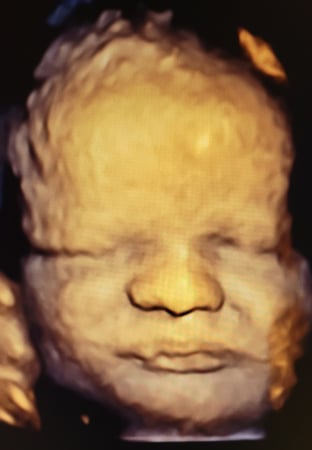

Tasha Crump, is registered by the American Registry of Diagnostic Medical Sonographers (ARDMS) and have over 18 years experience in medical diagnostic sonography specializing in Maternal Fetal Medicine. She is a highly proficient in the art of 3D 4D ultrasound. Tasha has practiced and trained in NYC's top ranked hospitals including Columbia Presbyterian. At Love at First Sight Imaging Studio you'll be in a very comfortable and calming atmosphere for you and your family to bond with your baby. We have state of the art equipment with HD Live to image unbelievably realistic views of your baby. You will fall in Love at First Sight.